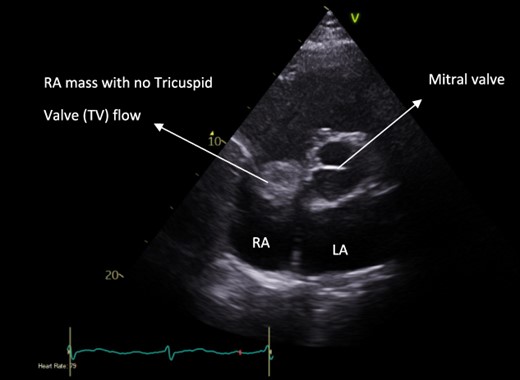

A 52-year-old gentleman was admitted to a district general hospital for shortness of breath causing type 1 respiratory failure with oxygen saturations of <90% despite high flow oxygen. His past medical history was unremarkable, and he was usually fit and well. A CT Pulmonary Angiogram (CTPA) was undertaken, which showed a heterogeneous oval-shaped lesion measuring 15 × 9 × 14 cm3 between the heart and the diaphragm, with a median attenuation of 35 HU and no enhancement during the arterial phase. Further solid lesions of 14 mm in the right lower lobe and 5 mm in the right upper lobe raised the suspicion of a primary cardiac sarcoma with pulmonary metastasis. This is shown in Fig. 1. Subsequent urgent CT staging (Fig. 2) was undertaken, which confirmed an indeterminate space occupying the inferior pericardial space, right atrial (RA) filling defect and anterior nodular pericardial thickening. No intra-abdominal or bone lesions were identified. An echocardiogram also confirmed these finding with the addition of no flow through the tricuspid valve (TV), as shown in Fig. 3.

Pre-operative apical four-chamber view echocardiogram showing RA bulk blocking TV flow.